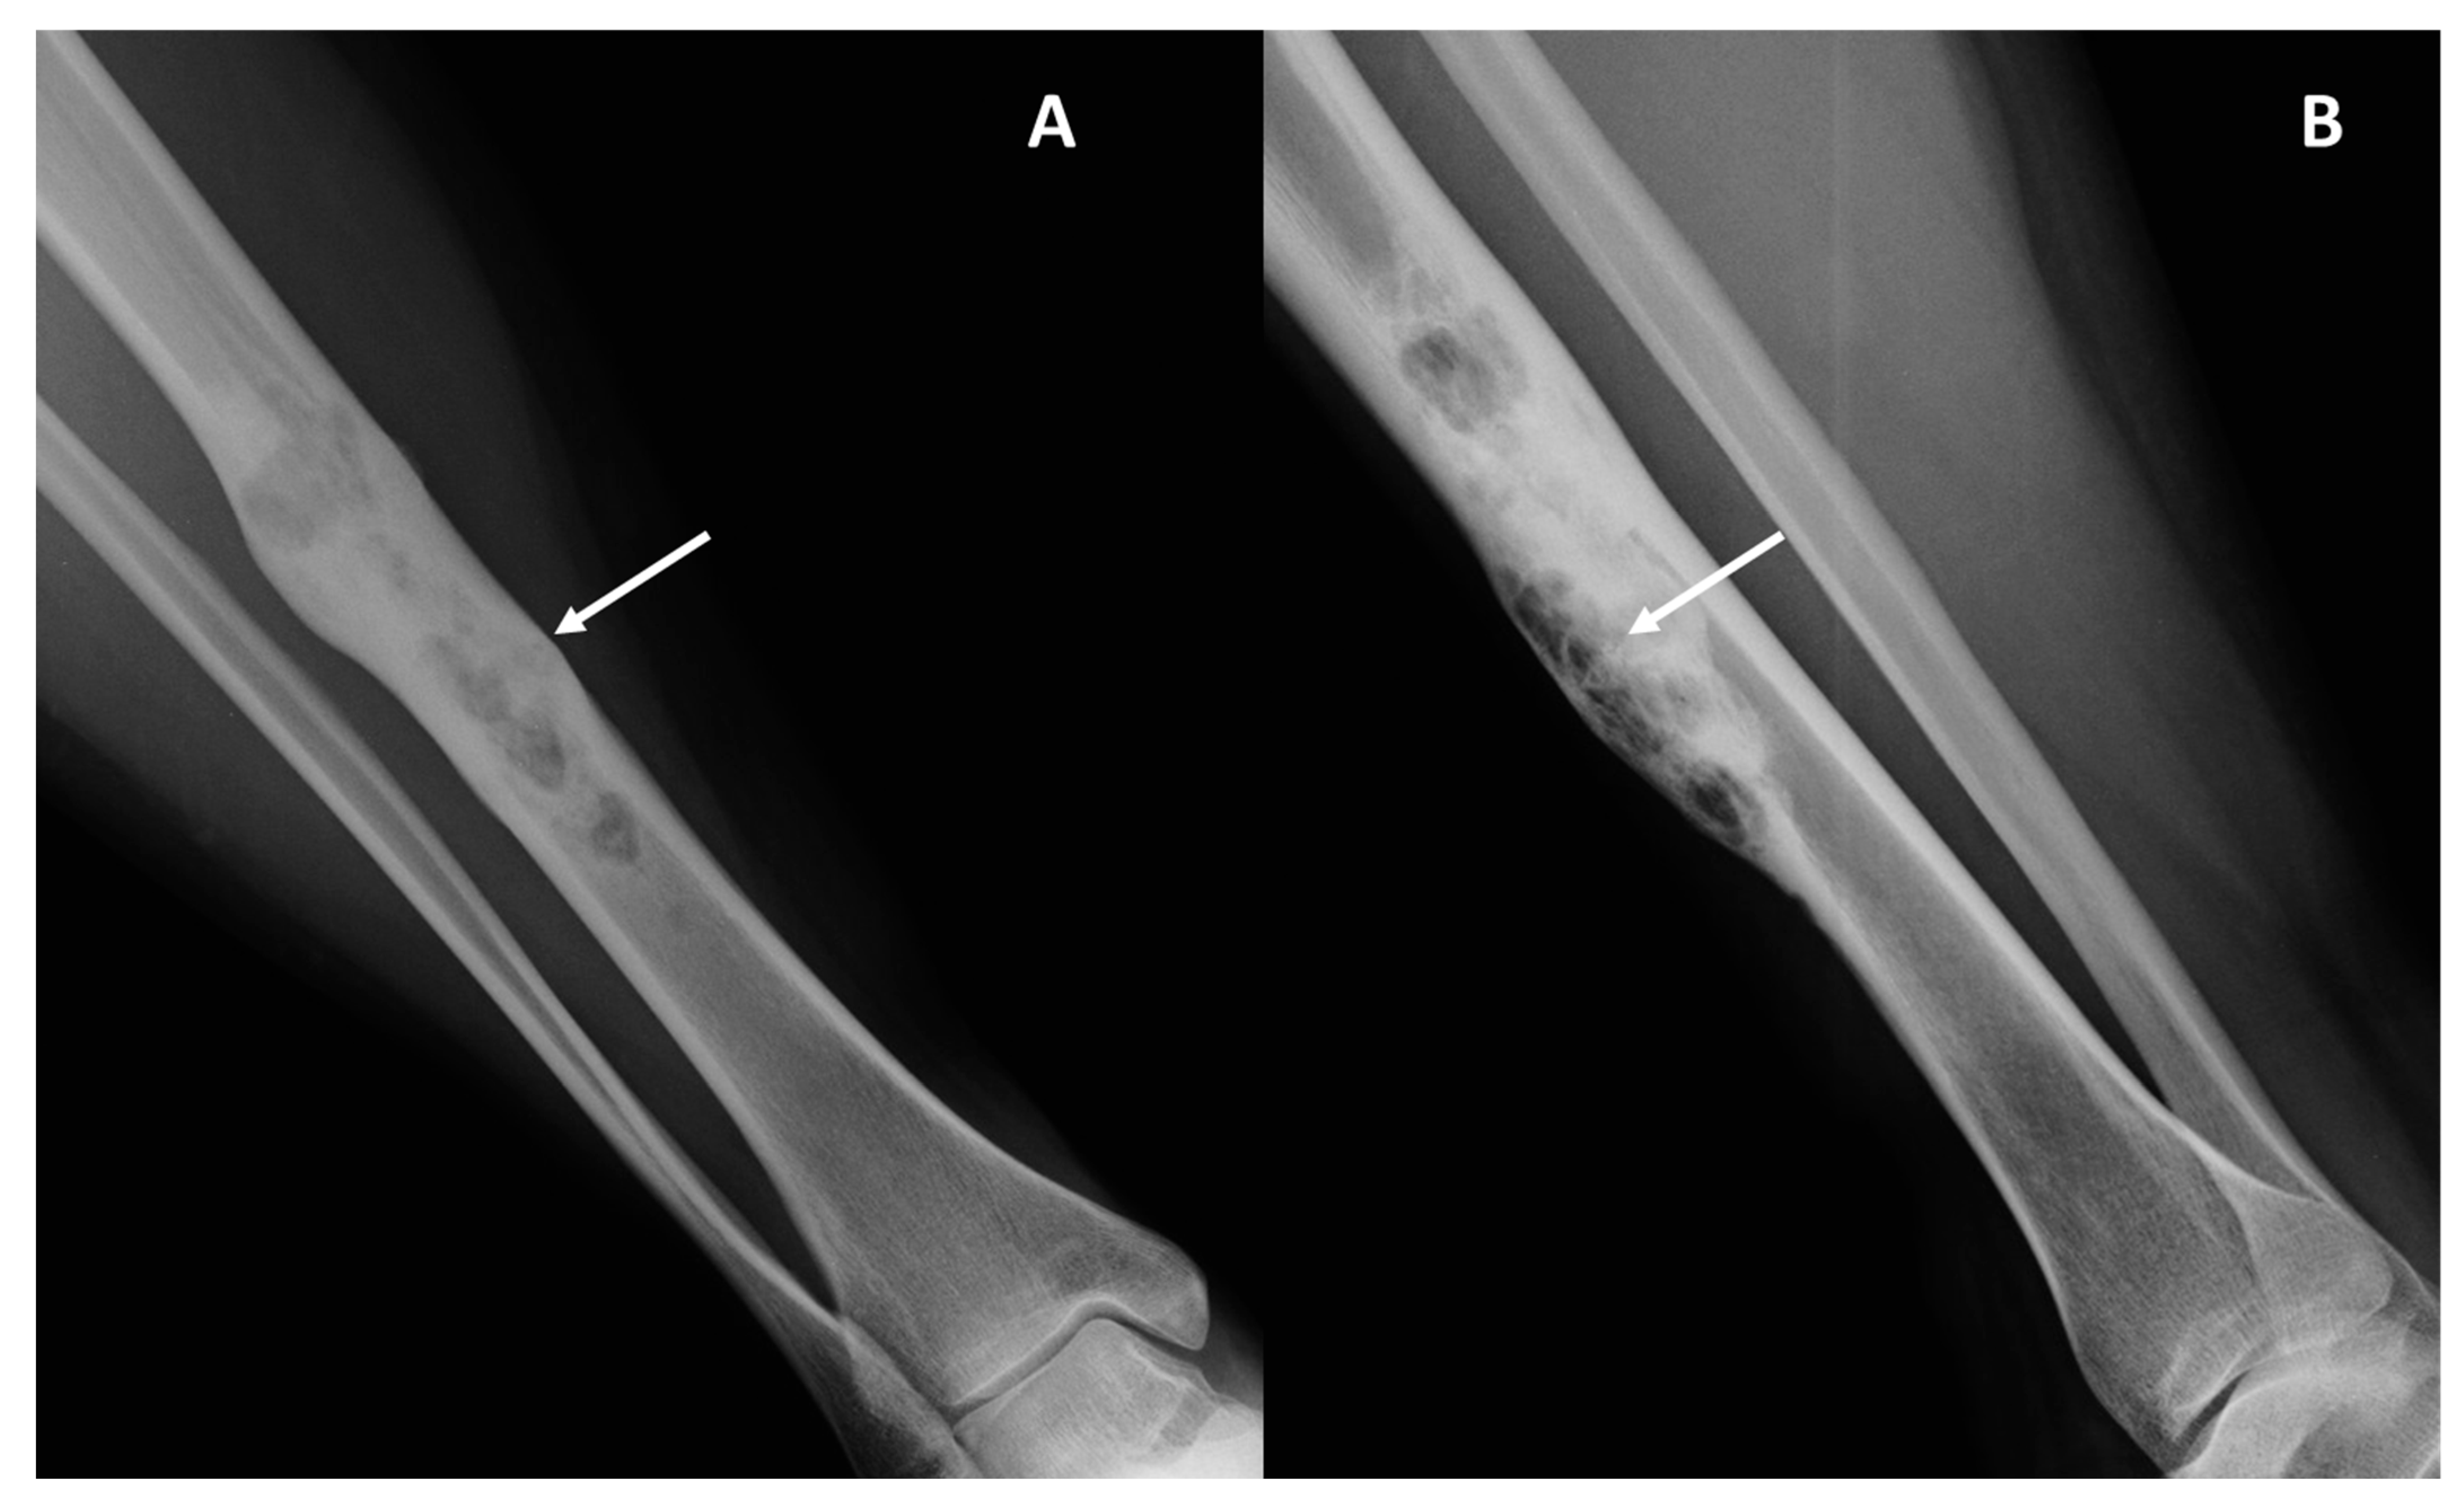

- Conventional radiography (CR) studies were performed with different equipment, with two orthogonal projections.

| Periosteal reaction: absent (0), non-aggressive (1), aggressive (2) | Absent (13), Non-aggressive (2), aggressive (1) | Absent (2), Non-aggressive (2), aggressive (2) | 0.24 |

| Extra-intra osseus extension: Intraosseous only (0), intra- and extra-osseous (1) | Intraosseous only (14), Extra-osseous (2) | Intraosseous only (0), extra-osseous (6) | 0.0004 * |